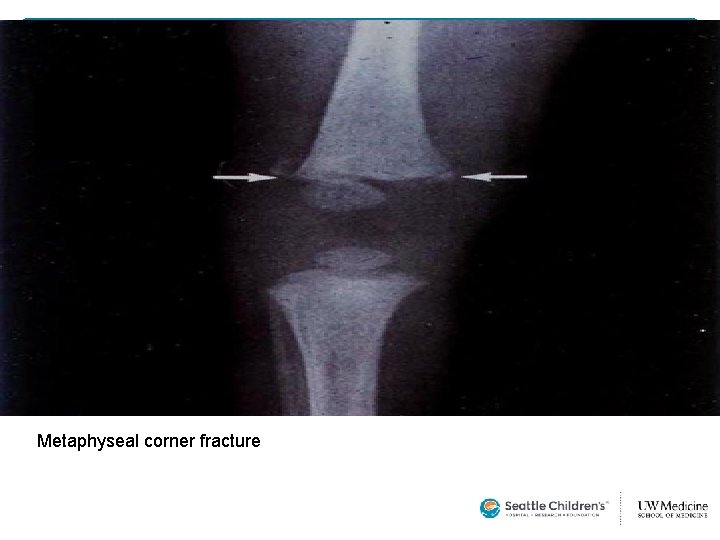

Metaphyseal corner fracture